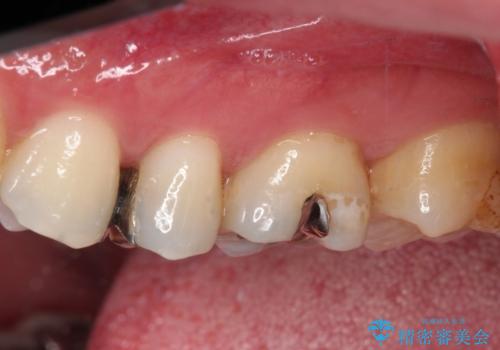

- 銀歯をセラミックにしたいとのことで来院された患者様です。

まず麻酔をして銀歯を外し、むし歯を除去し、形を整えて型取りします。

そして次の来院時、セラミックインレーを装着し、噛み合わせなどの調整を行います。

それを左右に分けて行いました。

インレーを装着するときは、唾液や血液による接着力の低下を避けるためにラバーダム防湿を行いました。